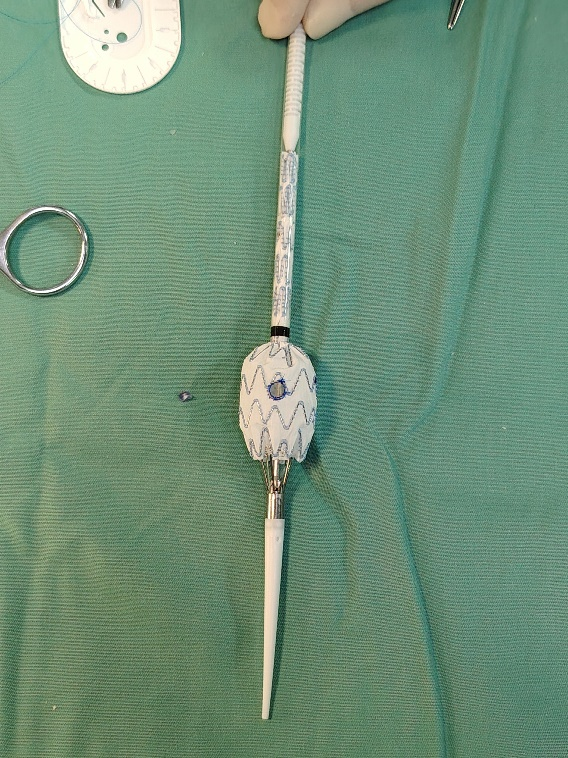

治疗方案:右入路上美敦力EIIs ESBF2314C103EE,对主体支架开窗束径保留肠系膜下动脉,左接髂支ETLW1616C93EE剪短3节。

• 美敦力IIs ESBF2314C103EE,ETLW1620C93EE

1.麻醉成功后,常规消毒铺巾,取美敦力腹主动脉分叉型支架(美敦力25-14-103)于体外送入3D打印模型内部分释放,肠系膜下动脉开口位置开窗,并缝合弹簧圈作标记,应用V18导丝束径,重装支架并排气。